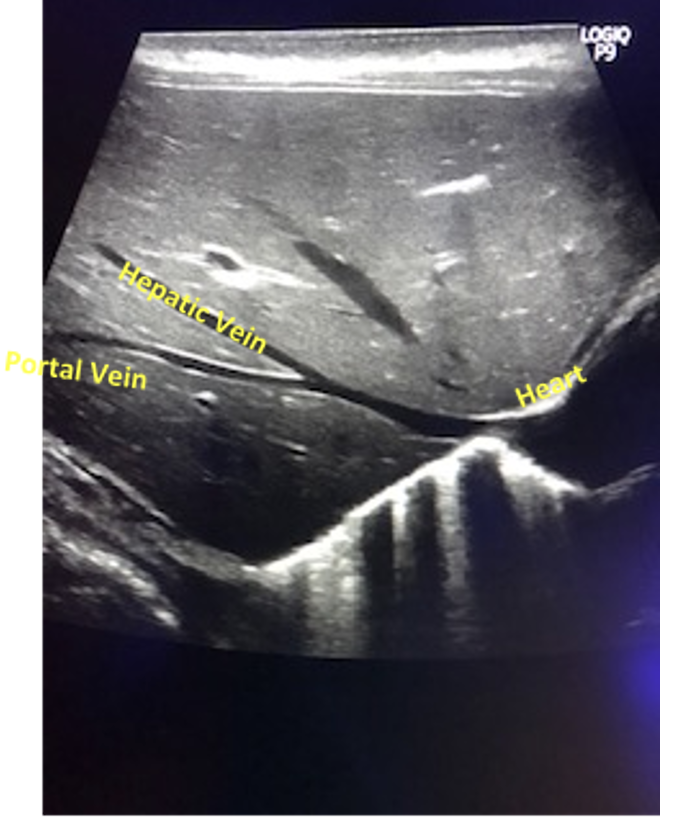

Further to this, the portal sinuses and hepatic veins are thick-walled and their echogenicity can give them a similar appearance to a catheter

Do not get confused with hepatic veins that lead into the cava-atrial junction too.